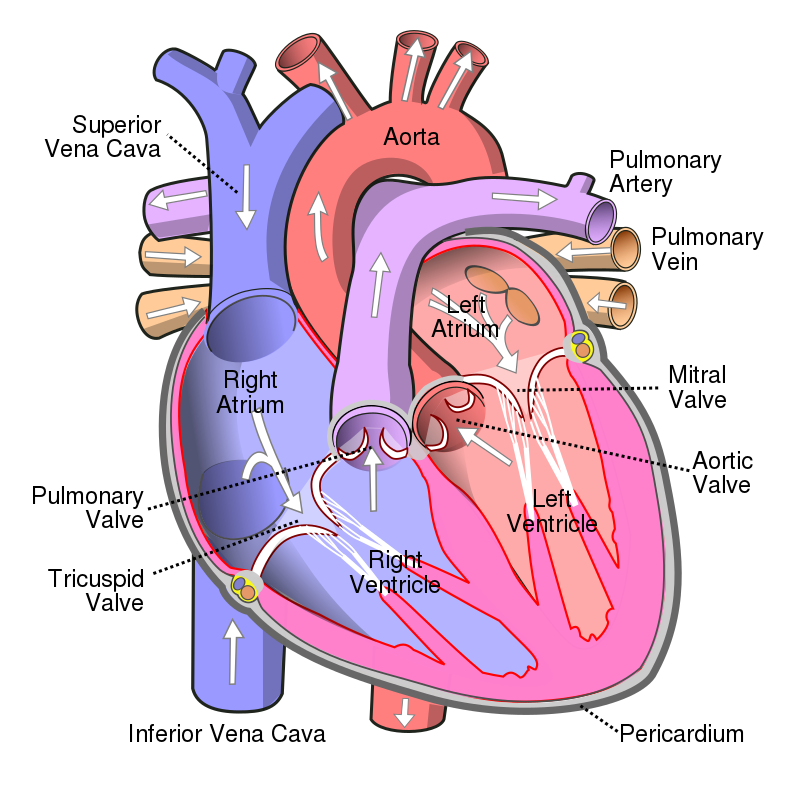

The heart has four valves:

- Aortic valve

- Pulmonic valve

- Tricuspid valve

- Mitral valve

The cardiac valves ideally prevent backflow.

Valvular lesions generally result in stenosis or regurgitation.

Aortic stenosis occurs when the aortic valve orifice narrows.

Aortic regurgitation is the backflow of blood from the aorta into the left ventricle during diastole caused by aortic root dilatation or valve damage.

Mitral valve prolapse is the ballooning of the mitral valve into the left atrium during systole.

Mitral regurgitation occurs when blood flows from the left ventricle into the left atrium during systole and is mainly caused by mitral valve prolapse.

The narrowing of the mitral valve orifice is known as mitral stenosis.